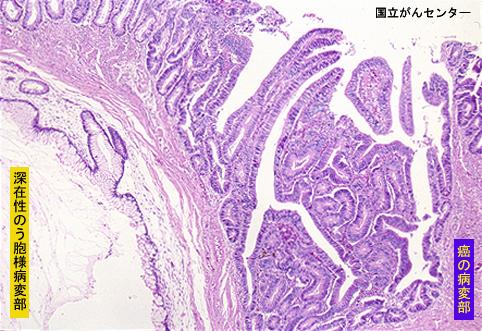

疾患(病理主体)の分類腫瘍様病変/大腸深在性のう胞症

部位(臓器別)大腸/下行

検査方法ミクロ

腫瘍の肉眼分類0型(表在型)/I型(Is)

病変の最大径(ミリ)15〜19

腫瘍の深達度sm